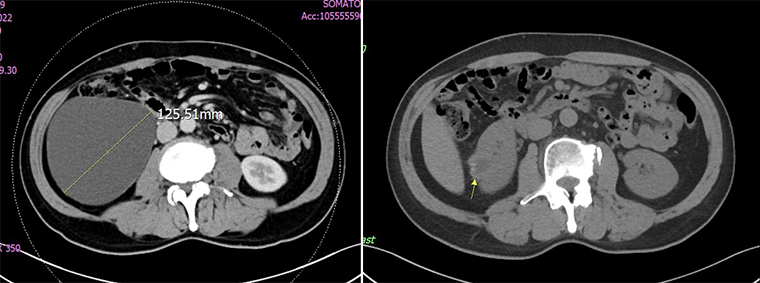

【NOW健康 翁靖祐/台南報導】62歲的吳先生,因右側腰痠腰痛持續3週而前往奇美醫療財團法人奇美醫院泌尿外科主任黃冠華門診就診,發現右側腎臟有1顆直徑達12公分的腎盂旁囊腫。吳先生選擇接受自然孔道無創腎內手術,手術後,吳先生於第2天便順利出院,腰痠腰痛的症狀完全消失,恢復日常生活,甚至開心地抱起了孫子也不會感到不適。

▲治療前(左)與治療後(右)對比。(圖/奇美醫院提供)